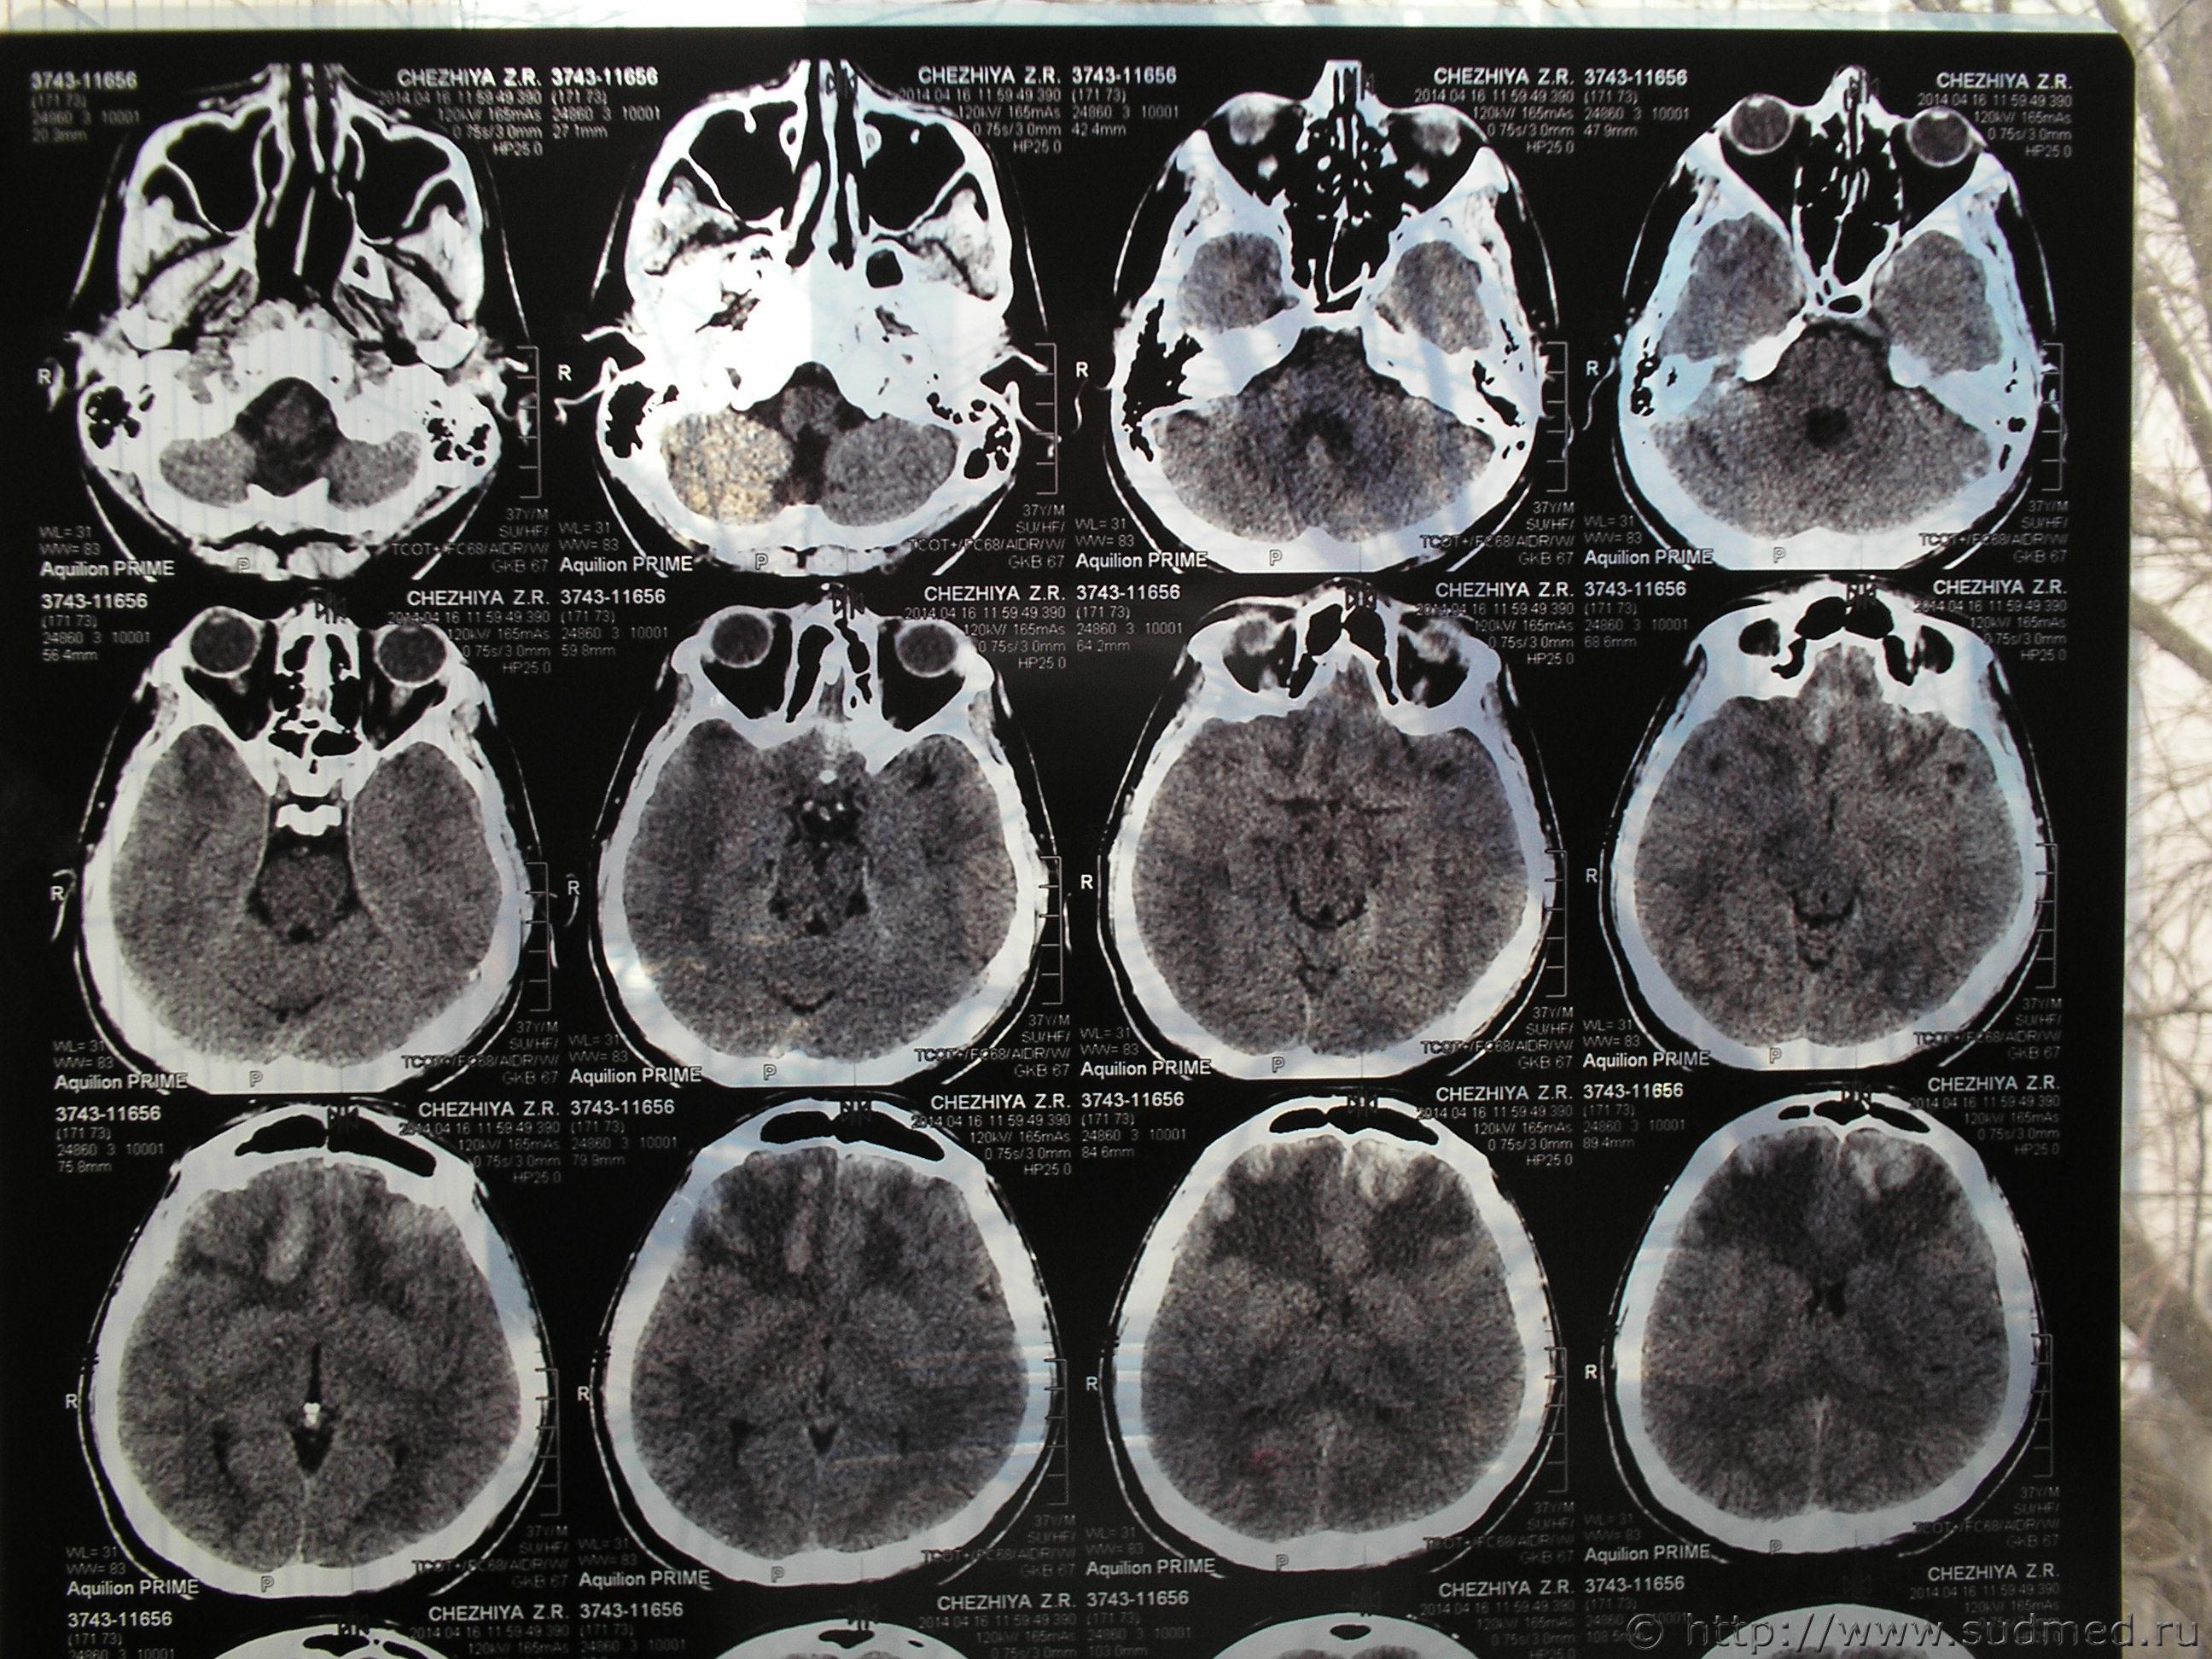

Нужно знать, что видно на данных снимках КТ. Спорная экспертиза. Делали по копии мед. карты и по этим снимкам. Снимки на руках у потерпевшего, еле достали. Исчез рентген потерпевшего из приемного отделения, осталась только запись в карте. Повреждений свода черепа не обнаружено. Диагноз в обвинении - Комплексный перелом свода и основания черепа, отоликворея слеа, УГМ средней тяжести, субарахноидальное кровоизлияние, пневмоцефалия, алкогольное опьянение, ушибленная рана на затылке. Потерпевший выписан из больницы на 18й день, более нигде не наблюдался. Говорит лечится в частном порядке. Мнение эксперта-рентгенолога - перелом клиновидной кости давностью не более 6-8 недель. А снимки сделаны в первые сутки. Есть еще пара снимков, но такого же качества и, как написано в экспертизе дополнительной информации не содержат. Очень нужно знать, что на снимках, независимое мнение. Есть еще снимок МРТ через три месяца. Информацию на дисках не предоставили.

Проконсультируйтесь с опытным рентгенологом, специалистом по КТ. Лучше - с двумя-тремя. Это придется сделать очно, т.к. информация существенно теряется: а) при перефотографировании пленок КТ, б) при пересылке через интернет этих фотографий. Полагаю, что приватным образом такую консультацию можно получить у любого подобного специалиста. Получить какое-то письменное заключение возможно при оформлении договорных отношений на кафедре рентгенологии мед.ВУЗа, в мед.центре, профилирующемся на КТ диагностике и т.д. Лучше представить ВСЕ снимки КТ (тогда более достоверно и аргументированно можно судить о динамике изменений, о давности травмы), все КТ на цифровом носителе (можно будет построить 3D-реформацию изображения, т.е. более детально определить распространение перелома).